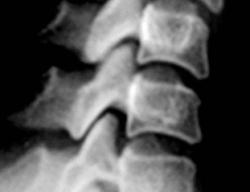

Иллюстрации 1, 2, 3. Определяется «выпрямленность» шейного лордоза, неравномерное сужение межпозвонковых щелей в сегментах С2-С3, С3-С4. Резкое сужение межпозвонковых щелей в сегментах С4-С5, С5-С6, С6-С7, с выраженным субхондральным склерозом тел позвонков, неровностью замыкательных пластинок, образованием остроконечных остеофитов по передней поверхности тел позвонков. В дугоотросчатых суставах определяется сужение суставных щелей с выраженным субхондральным склерозом. На иллюстрации 2 хорошо дифференцируется остеосклеротическая перестройка тел С4, С5, С6, С7, как компенсаторная приспособительная реакция, в результате анатомической и функциональной несостоятельности межпозвонковых дисков.